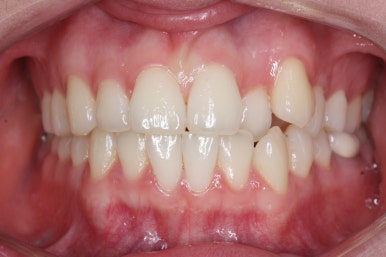

위아랫니가 매우 가지런해졌고 고민하셨던 덧니도 말끔히 개선되었습니다.

전후 사진을 비교해 보겠습니다.

14개월만에 치아는 가지런해졌고, 위아래 치열의 중앙도 맞아졌으며 발치를 하지 않았음에도 치열이 뻐드러지거나 돌출되지 않았습니다.

전반적으로 매우 좋아졌습니다.

또한 오히려 부각되었던 대문니의 뻐드러짐이 치료 후 개선이 되었고 웃는 모습도 굉장히 예뻐졌습니다.